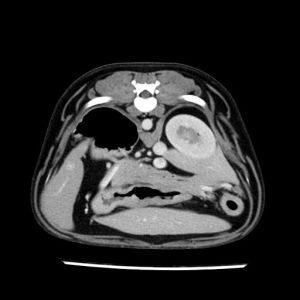

La lesione focale epatica , la ceus,la Tac e il chirurgo .